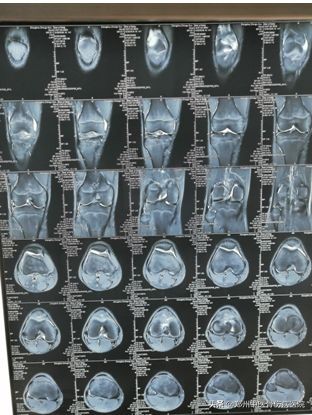

2019年12月21日,14岁的航航在背着同学练习负重蹲起后,出现右腿部僵硬、屈曲及伸直均疼痛的症状。即来我院就诊,检查结果为,右下肢 X线片无异常,右膝MRI片示:右膝关节腔及髌上囊积液。

患者片子